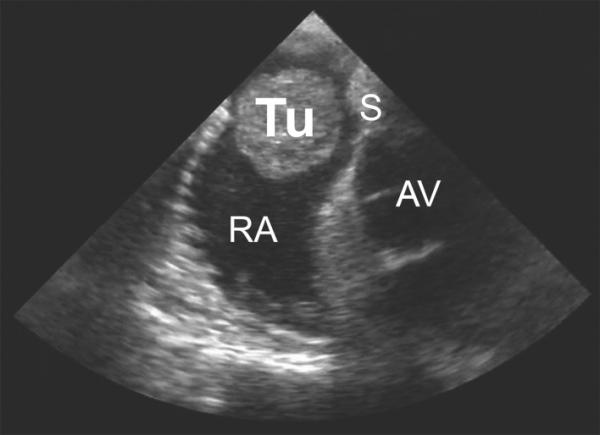

心臟腫瘤,無論良性還是惡性,臨床上都比較少見,屍檢發現心臟腫瘤的發病率約為0.02%,其中良性佔75%,惡性佔25%。其中粘液瘤是最常見的心臟原發性腫瘤,佔原發性心臟腫瘤的50~70%,而血管肉瘤是最常見的心臟惡性腫瘤,在心臟原發性腫瘤中所佔的比例僅次於粘液瘤,約佔心臟惡性腫瘤的30%。

心臟腫瘤往往缺乏特異性的臨床表現,其診斷往往需要藉助超聲心動圖、CT或MR才能確診,容易造成誤診或漏診。